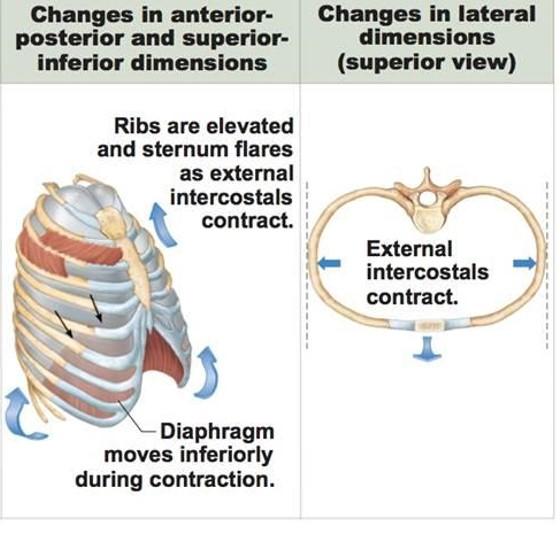

what is one abnormal movement pattern of ventilation? who typically displays this?

name another abnormal ventilation quality? when do you typically see this with?

“Shrug” shoulders...Patients with COPD and other pulmonary disease may display this type of breathing pattern

Asymmetry... see this with trauma/pathology to one lung

- Ex: pneumothorax, etc…